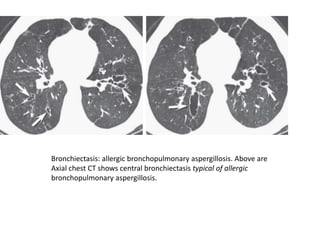

Bronchiectasis: allergic bronchopulmonary aspergillosis. Above are

Axial chest CT shows central bronchiectasis typical of allergic

bronchopulmonary aspergillosis.

Bronchiectasis: allergic bronchopulmonaryaspergillosis. Above are Axial chest CT shows central bronchiectasis typical of allergic bronchopulmonary aspergillosis.